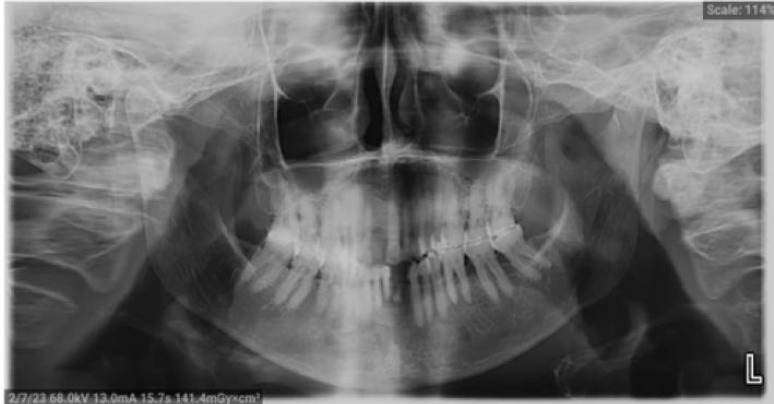

Materials & methods: We present a case of HZ infection affecting the mandibular division of trigeminal nerve in a 78-year-old widow. The patient presented with multiple complications including hyper- pigmented scarring, post herpetic neuralgia and chronic non-suppurative osteomyelitis of the left mandible. This case report highlights the presentation of multiple complications from HZ infection especially among the elderly.